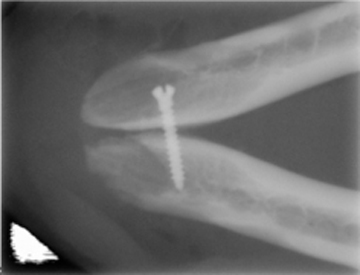

Los mismos principios rigen la cirugía ortognática y la cirugía maxilofacial pero cada una tiene su área de función. La cirugía ortognática la realizamos cuando un paciente presenta una discrepancia exagerada en la relación entre el maxilar con la mandíbula y que le ocasiona un problema funcional severo, por lo que se realiza ya sea la reducción o el aumento antero posterior o lateral del maxilar o la mandíbula con el fin de inter relacionar adecuadamente los dos macizos óseos. Por lo regular, lo más común es que la cirugía ortognática se realice de manera electiva. En cambio la cirugía maxilofacial lo que tratamos es de mantener la integridad estructural y funcional de las estructuras maxilofaciales por lo que la mayoría de las veces es una cirugía de emergencia y a veces electiva. Dentro de la cirugía maxilofacial entra la remoci ón de tumores de extensión amplia, la cirugía ortopédica y la reconstrucción de defectos óseos. En la reconstrucción de defectos óseos usamos la tecnología médica de punta para eficientar los procesos de cicatrización. Ofrecemos la colocación del Plasma Rico en Plaquetas el cual es un producto homólogo que permite acelerar y mejorar la cicatrización ósea. También usamos membranas de colágeno, xenoinjertos de cualquier forma y tamaño para la reconstrucción de cualquier estructura ósea. La estabilidad de la mandíbula a veces se ve comprometida en las fracturas donde existe pérdida de sustancia ósea por enfermedad periodontal o por uso de armas de fuego por lo que podemos reconstruir usando miniplacas y tornillos de titanio que se osteointegran al hueso y no es necesario retirarlos ya que mantendrán por toda la vida del paciente la estabilidad de sus hueso fracturados. También colocamos miniplacas y tornillos de poliglicolato que se reabsorben en corto, mediano y largo plazo. También proporcionamos el servicio del láser terapéutico para mejorar la reparación y eliminar dolor posoperatorio.

Separación de Sinfisis mandibular por enfermedad periodontal. Colocación de tornillo de titianio